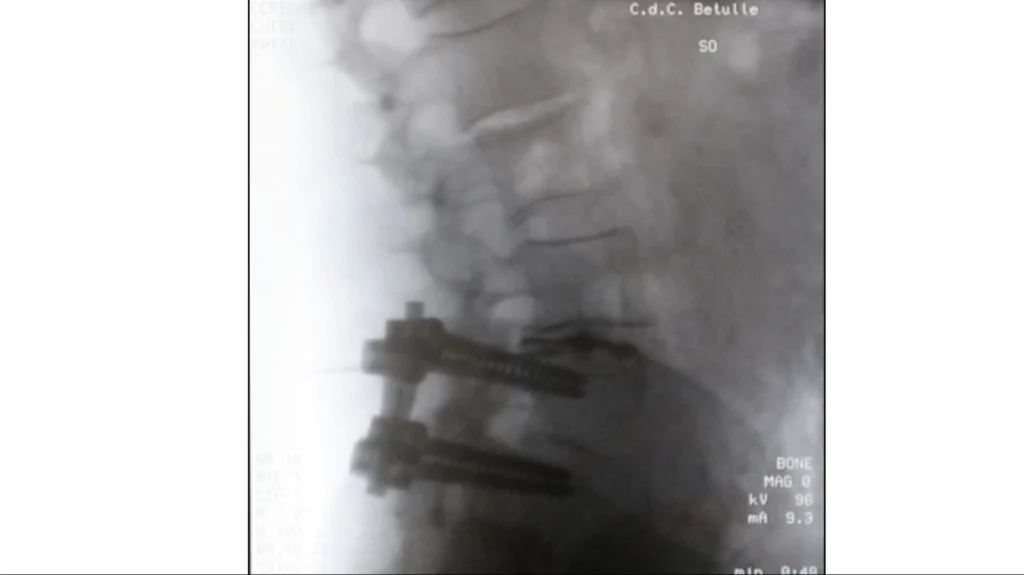

Sotto guida fluoroscopica, l’ago per decompressione discale utilizza il principio della pompa di

Archimede per rimuovere il materiale sporgente dal disco o un’ernia discale contenuta, riducendo

la pressione nel disco e la zona circostante, fornendo sollievo dal dolore.